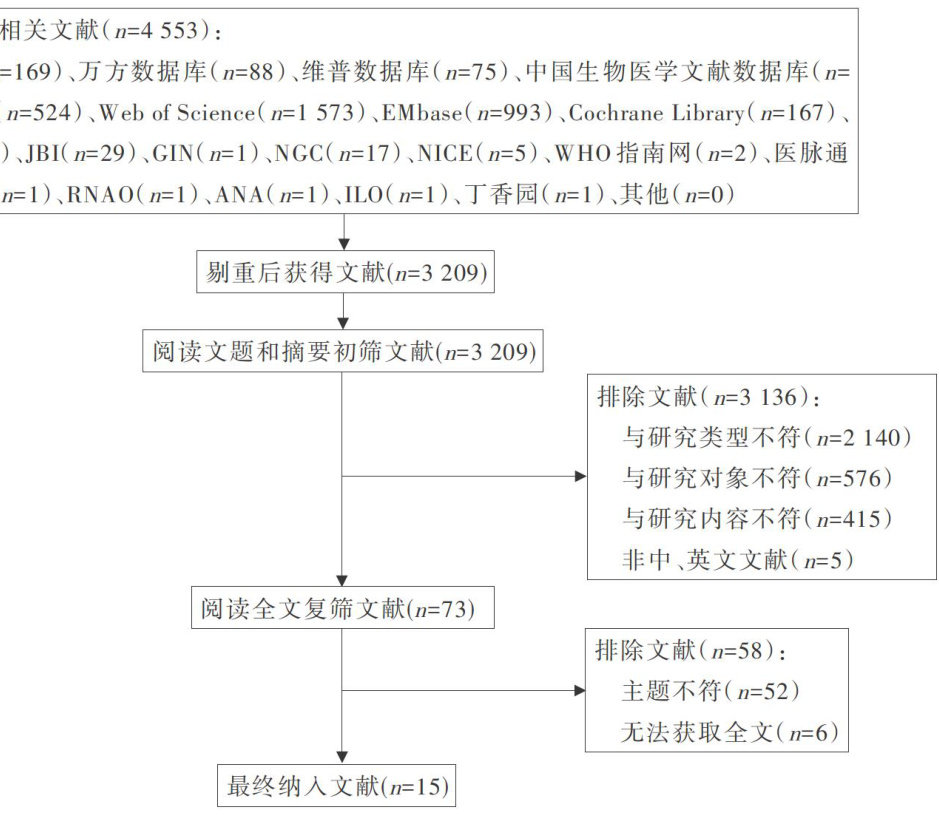

科研论著 | 临床护士工作场所暴力预防及管理的最佳证据总结

科研论著 | 临床护士工作场所暴力预防及管理的最佳证据总结